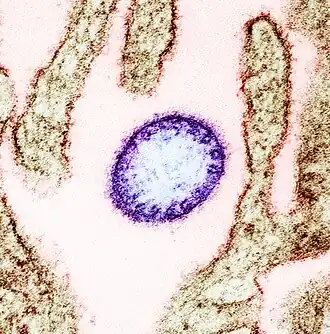

Das Nipah-Virus (NiV, auch NIPV, Spezies Henipavirus nipahense) ist ein Virus aus der Familie Paramyxoviridae,[3][4] das beim Menschen eine häufig tödlich verlaufende Gehirnentzündung (Enzephalitis) auslösen kann. Das Nipah-Virus tritt insbesondere in Südasien und Südostasien auf und kann durch Kontakt mit Körperflüssigkeiten und -ausscheidungen infizierter Tiere, Menschen oder Reservoirwirte oder dem Verzehr von kontaminierten Lebensmitteln übertragen werden. Reservoirwirte sind fruchtfressende Flughunde der Gattung Pteropus, die in Süd- und Südostasien sowie auf Madagaskar vorkommen. Diese Flughunde scheiden das Virus z. B. über Urin und Speichel aus und übertragen es in der Regel auf andere Tiere (insbesondere Schweine), die es auf den Menschen weiterübertragen.[5]

Das Nipah-Virus bildet zusammen mit dem eng verwandten Hendra-Virus die Gattung Henipavirus in der Familie der Paramyxoviridae. Es wurde erstmals 1999 im Zuge der Untersuchungen des Ausbruchs in Malaysia und Singapur charakterisiert.[6] Das isolierte Virus war morphologisch dem kurz zuvor in Australien entdeckten Hendra-Virus sehr ähnlich, jedoch im Krankheitsverlauf und seiner Antigenität doch von diesem verschieden. Es wurde daher vor einer endgültigen Benennung zunächst als Hendra-like Virus bezeichnet. Das neue Virus erhielt seinen taxonomischen Namen in Anlehnung an den kleinen Ort Kampung Teluk Nipah auf der malayischen Insel Pangkor, wo die Epidemie von 1998 besonders hohe Infektionszahlen aufwies und das Virus aus einem von dort stammenden Patienten isoliert wurde.